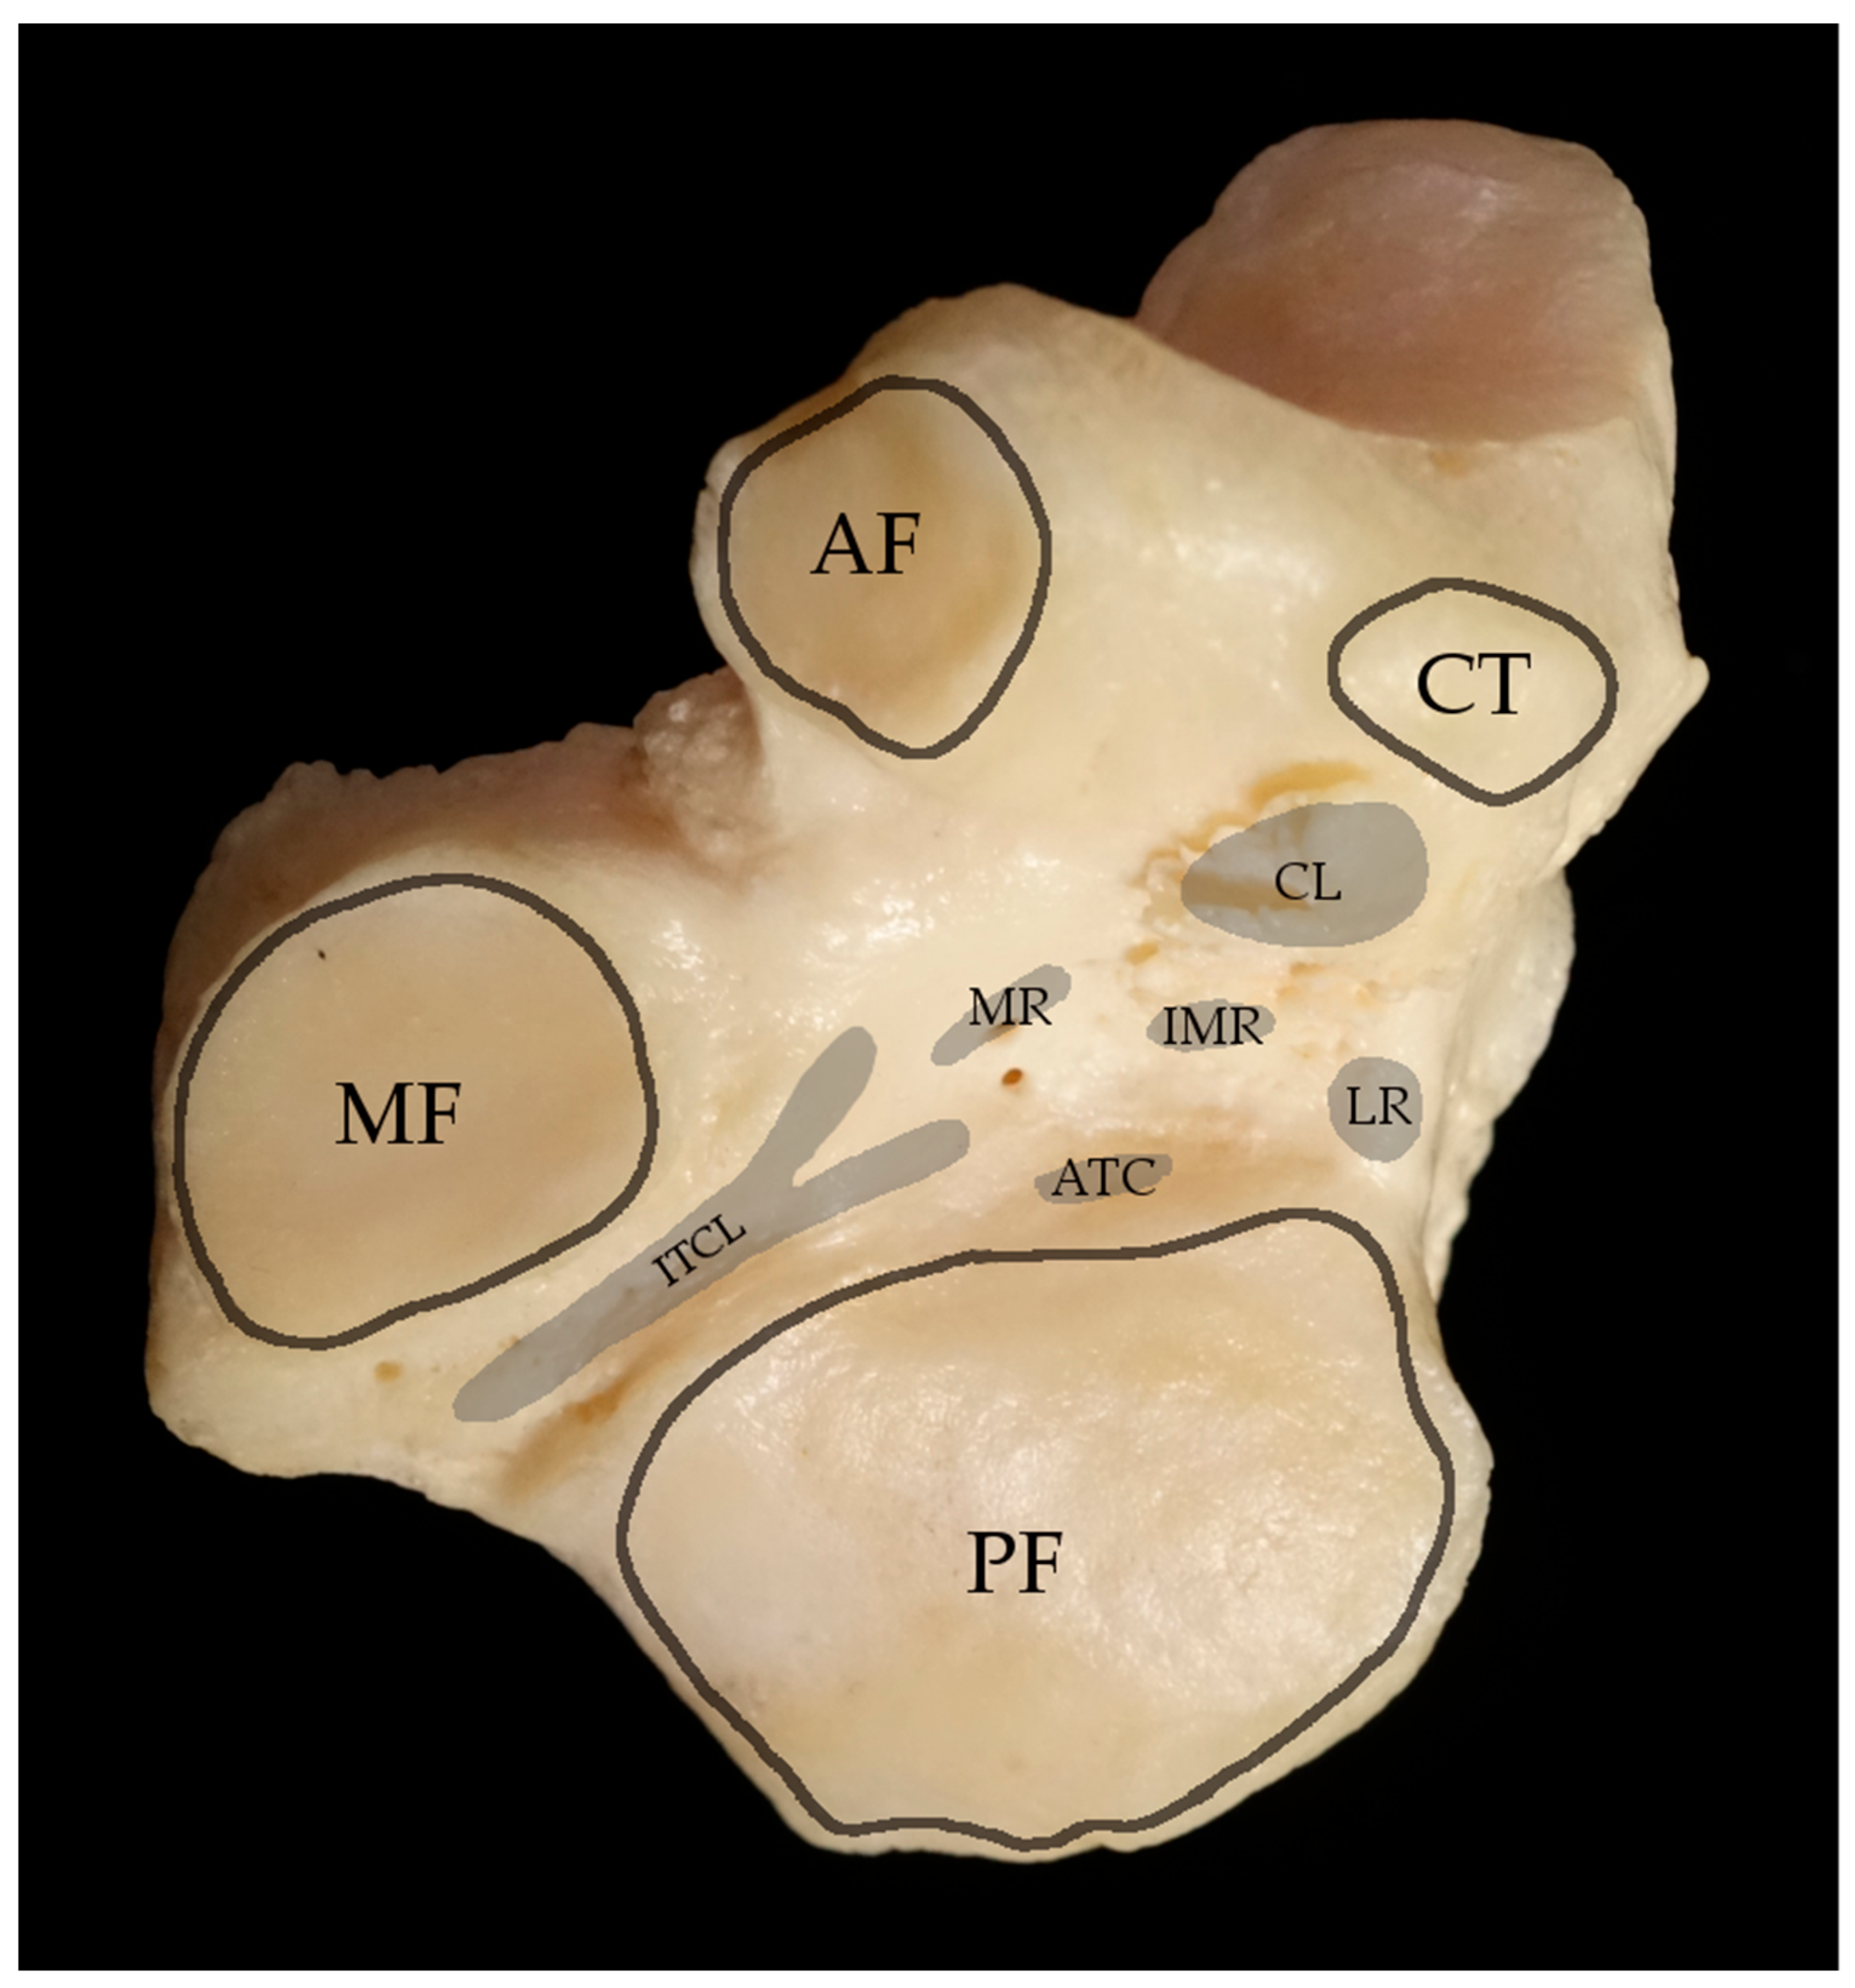

3.1. Anatomy